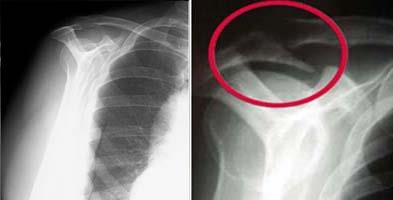

Radiografías. Como las radiografías no muestran los tejidos blandos del hombro, como el manguito de los rotadores, las radiografías simples de un hombro con dolor en el manguito son muy frecuentes o pueden mostrar un pequeño espolón óseo. Una vista especial de la radiografía, llamada anteroposterior, mostrará un pequeño espolón óseo en el borde frontal del acromion.

(Izquierda) Radiografía con outlet view normal. (Derecha) Outlet view anormal que muestra una protuberancia ósea grande que causa compresión del manguito rotador.